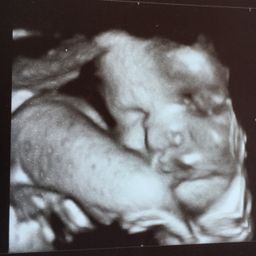

Fetal Development What Your Baby Looks Like This

Fetal Development What Your Baby Looks Like This from slidetodoc.com